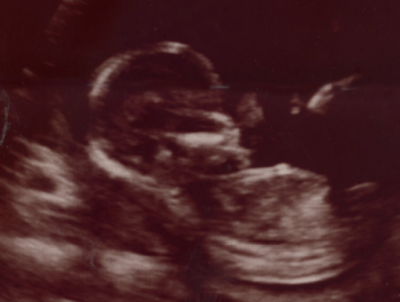

October 15, 2019 – West Bend, WI –Grace Isabel Michelle Marquez, infant daughter of Teilor Larson and Miguel Marquez, was a stillborn passing on Wednesday, October 9, 2019 at Froedtert Hospital in Milwaukee.